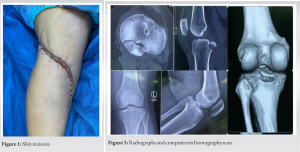

A knotless fixation was planned with two swivel lock PEEK anchors (4.9 mm, Arthrex, Naples, Florida). Two drill holes were made and the drill holes were tapped for the passage of anchors. The sutures that were passed through the capsule and PCL were then passed through the anchors, with two sets of sutures through each anchor. The anchor along with the sutures was threaded through the posterior tibial cortex with sutures in tension and the K wire was removed (Fig. 5). The reduction was checked under the image (Fig. 6) and the tourniquet deflated. The wound was washed and closed in layers. A posterior knee plaster was applied with a proximal tibial posterior padding to prevent posterior sagging. The patient was started on isometric quadriceps exercises from day 1 and non-weight-bearing crutch walking was also started. At 2 weeks, the plaster was removed and sutures were also removed.

A brace was applied with proximal leg PCL support and non-weight bearing was allowed along with isometric quadriceps and ankle range of movement exercises. At 4 weeks, partial weight bearing was allowed progressing to full weight bearing by 8 weeks. The patient was started on an open chain range of movement exercises of the knee and active straight leg rising. Night-time bracing was continued for 2 months. At 6-month and 1-year follow-up, the patient had no complaints and she achieved her full range of movement (Fig. 7). There was no posterior tibial sag.